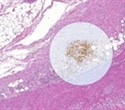

The patented technology is used in the 3D histology software Voloom® to enable fast 3D reconstructions from serial sections. Voloom can reconstruct 3D volumes in a matter of minutes and by this enables researchers to effectively use 3D reconstructions in their daily workflows.

Slidematch™, the latest addition to the microDimensions product line, uses the registration technology for the alignment of differently stained sections to perform e.g. multiplex analysis or compute scores for improved cancer classification.